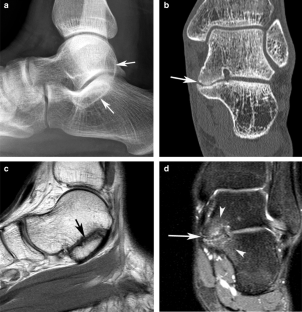

Fig. 1

Fig. 2

Fig. 3

Fig. 4

Fig. 5

Fig. 6

Fig. 7